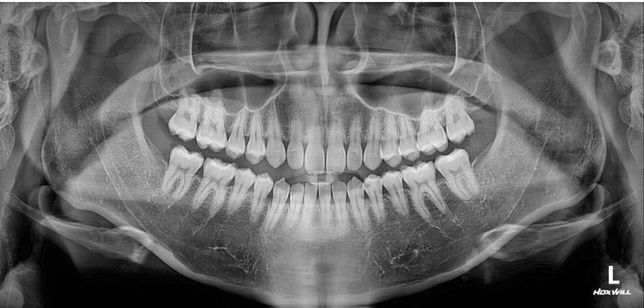

- 치과의료상담Q. 제 옆모습을 가끔 보면 턱이랑 입이 나온것같아보이는데 전문의가 평가하기에도 그런지 알고싶어요질문1. 제 옆모습을 가끔 보면 턱이랑 입이 나온것같아보이는데 전문의가 평가하기에도 그런지 알고싶어요가끔 사진찍히거나 거울볼때 옆모습이 입이랑 턱이 남들보다 나온것같다는 생각이들거든요 이런게 주걱턱인가? 이게 치과에 문의하는게 맞는지 모르겠지만 전문의님 개인평가를 듣고싶어요~ 나중에 구강악쪽 양악수술 상담한번 받아보려고요질문2. 만약 입만 넣는다면 발치없이 인비절라인 같은 투명교정으로도 가능할까요?질문3. 제 앞니 치근이 짧나요?이미지가 포함된 질문이에요.

- 치과의료상담Q. 중안면부 꺼짐있는경우 양악을 하면 개선이 되나요?중안면부 꺼짐있는 경우 미용적인 목적으로 양악수술을 하면 개선이 되나요?보통은 이런경우 코수술을 하게되나요?치아 교합은 정상인데 일자목이라서 그런건지모르겠지만 옆모습을 봤을때 입체적이지 않고 약간 1자 모습? \\모양 이여서 콤플렉스입니다.오히려 이런경우 부작용이 크나요?자료가 부족하겠지만 그냥 의사님들 개인생각 적어주시면 도움이될것같습니다지인분들마다 평가하시는게 달라서 저스스로도 수술고민하는게 맞는지 잘모르겠습니다 (남자라서 괜찮다, 전혀모르겠다, 약간 턱이 나온것같다, 입이나온거다,연예인할것도 아닌데 왜그러냐 등등)그리고 제가 살짝 팔랑귀라서 고민하게되네요이미지가 포함된 질문이에요.

- 성형외과의료상담Q. 턱 돌출 성형 및 구강악 수술에대한 문의아하에 치과쪽에 질문을 자주애용해서 여기에 의사님들 개인적인 의견을 여쭙고자 질문남깁니다구강악외과에서 턱정밀상담 결과 하관평균길이가 성인남성평균보다 길고 돌출되었다고 들은 이후에 신경이 쓰여 수술 질문좀 하고싶습니다의사분께서는 기능적으로 이상은 없다고 수술을 권장하지는 않았습니다 미용적인거라고해서..아하 의사님들 개인적인 생각으로는 하관 수술하면 괜찮아질까요?그리고 돌출된 턱만 따로 수술가능한가요?수술이란게 기능개선이 주목적인데 저는 미용목적이니 괜히 할려고 고민하는게 아닌가 걱정되어서요양악수술이나 하관수술해서 괜히 후회할까봐서요실제와 사진은 다르겠지만 ct와사진만보고 개인적은 의견 적어주시면 참고하도록 하겠습니다댓글달아주시는 의사님들 감사합니다^^이미지가 포함된 질문이에요.